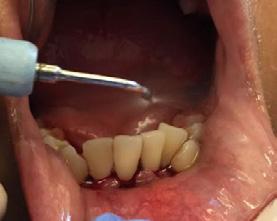

Se presenta un paciente de 29 años de edad. Al interrogatorio clínico refiere no tener alteraciones sistémicas y que actualmente no está tomando ningun medicamento, acude a la consulta odontológica para que le realisen una limpieza. En la revision clínica se observa la presencia de bioplaca y con sarro en los organos dentarios (OD) del 32 y 42 por la superficie vestibular. Por lo que se indica una profilaxis, se procedió de la siguiente manera, tinción de la bioplaca (Figura 1), realizándose el levenatmiento del índice epidemiológico IHOS. Se obtuvo el promedio de

Dentista y Paciente 46 Caso clínico

Figura 1. Frente de inicio.

A B

Figura 2. Vista lingual inferior dientes con sarro.

la bioplaca, el cual fue bajo según el IHOS 0.6 y el sarro se localizó en los OD Inferiores 32 y 42 por las superficies vestibular y lingual.

En la Figura 2 se ven los organos dentarios del 32 al 42 con sarro en la superficie lingual abarcando menos del tercio medio.

Se llevó a cabo la profilaxis para retirar el sarro (Figura 3), una vez eliminado se procedió al cepillado de todas las superficies dentarias.

Una vez terminada la limpieza dental se revisó la técnica de cepillado que llevaba a cabo el paciente, la cual era adecuada. Se le indicó que para evitar la acumulación del sarro la utilización de auxiliares de limpieza como parte de las acciones de promoción de salud (Figura 4). Y el alumno de primer año le enseño el manejo del hilo dental como complemento para el control de bioplaca. Citando nuevamente al paciente al mes del tratmiento.